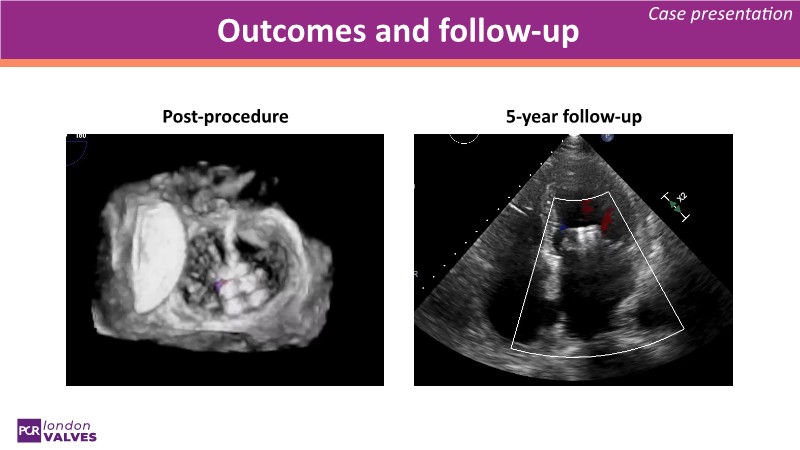

This session explores a full spectrum of therapeutic options for mitral and tricuspid regurgitation, focusing on the PASCAL Precision system for targeted repair and the SAPIEN M3 transcatheter mitral valve replacement. Through beating heart simulators, case discussions, and clinical evidence, participants will understand the versatility and unique features of these advanced interventions.